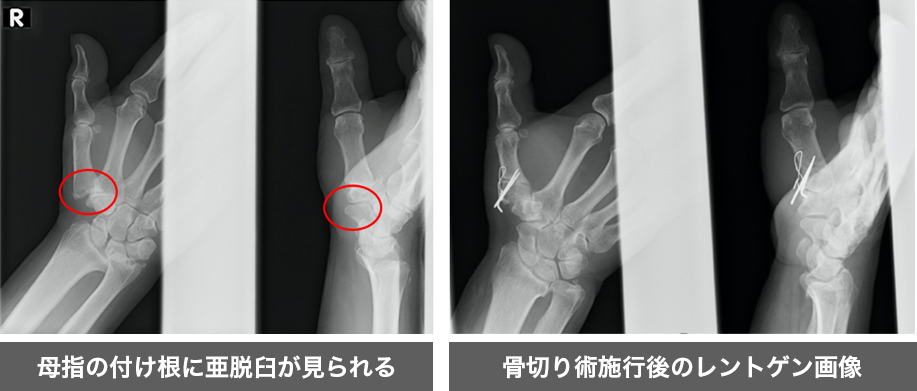

加齢や使いすぎにより母指の付け根の関節の亜脱臼(ずれ)や軟骨がすり減っていき、痛みを引き起こす疾患です。

初期では重たいものを持つ、母指・示指で物をつまむ、瓶のフタを空ける際に痛みを生じますが、進行してくると母指の変形を来したり、母指が開かなくなってきます。

当院では注射やリハビリテーション(運動療法・装具療法)の保存療法を行い、改善が見られない場合には骨切り術を行なっております。骨切り術とはアライメント(骨の形状)が崩れた骨を適切な形に調整するように骨切りを行い、母指を開くようにし(拡げる)、亜脱臼の改善を目指す手術です。